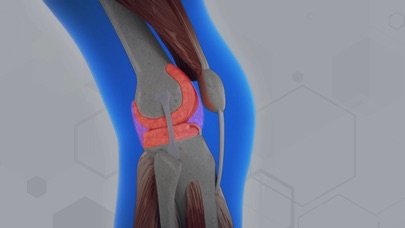

HA Counsellor is an app designed for Alkem. This app will let the doctors help their patients understand in detail about Knee Osteoarthritis. The app explains the difference between a Healthy and Osteoarthritic Knee, and common treatment options.